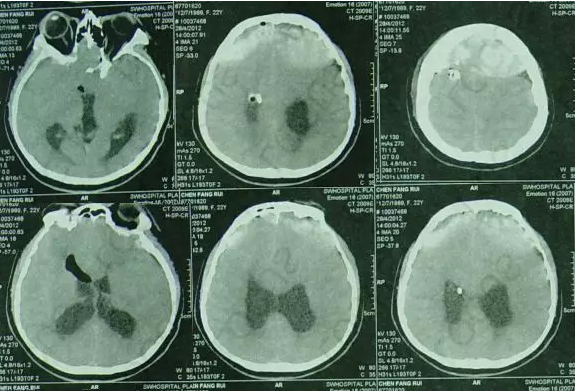

但内镜造瘘术后2小时出现了癫痫发作,意识模糊,查头颅CT:内镜造瘘术后状态,双额部硬膜下血肿(图-1)。

图-1:2012年4月28日头CT

内镜造瘘术后当天再次开颅进行了硬膜下血肿清除术,并留置右侧侧脑室外引流管,术后患者意识变清,查头颅CT:血肿基本消失(图-2)。

图-2:2012年4月28日开颅术后头CT

内镜造瘘术后第2天即2012年4月30日,行头颅CT:“三脑室内缩小”(图-3),进行腰穿检查颅内压为170mmH20,随拔除脑室外引流管。

图-3:2012年4月30日头CT